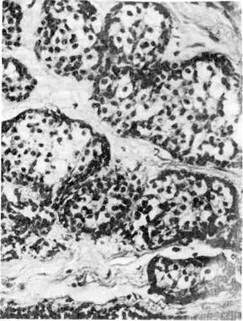

1. «Рак на месте», или carcinoma in situ (интраэпителиальная,

Рис. 138. Рак на месте

(carcinoma in situ).

с атипичными митозами (рис. 138). Рост опухоли происходит в пределах эпи-

телиального пласта, без перехода в подлежащую ткань. Эта форма рака опи-

сана и подробно изучена в шейке матки, описана в слизистой оболочке горта-

ни, желудка. Неинвазивный рак — этап роста опухоли. Со временем он

становится инфильтрирующим (инвазивным).